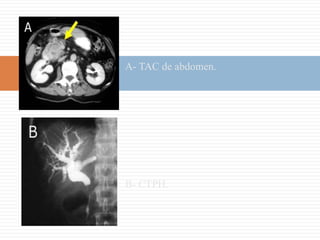

Colecistitis AgudaColecistitis Aguda LitiásicaSignos característicos:- Litiasis (cálculo impactado en el bacinete)- Engrosamiento de la pared vesicular (> de 3 mm.)- Bilis ecogénica- Dilatación en diámetro transversal > 5 mm- Signo de Murphy (+)La principal causa de colecistitis aguda es la litiasis, es muy raro que sea alitiásica.

Colecistitis Aguda AlitiásicaA y B- En este caso en la eco se ven sólo 2 de los 5 signos clásicos (bilis ecogénica y engrosamiento de la pared vesicular.)

Colecistitis AgudaColecistitis AgudaLitiásicaSignos característicos:- Litiasis (cálculo impactado en el bacinete)- Engrosamiento de la pared vesicular (> de 3 mm.)- Bilis ecogénica- Dilatación en diámetro transversal > 5 mm- Signo de Murphy (+)La principal causa de colecistitis aguda es la litiasis, es muy raro que sea alitiásica.

Colecistitis Aguda AlitiásicaAy B- En este caso en la eco se ven sólo 2 de los 5 signos clásicos (bilis ecogénica y engrosamiento de la pared vesicular.)